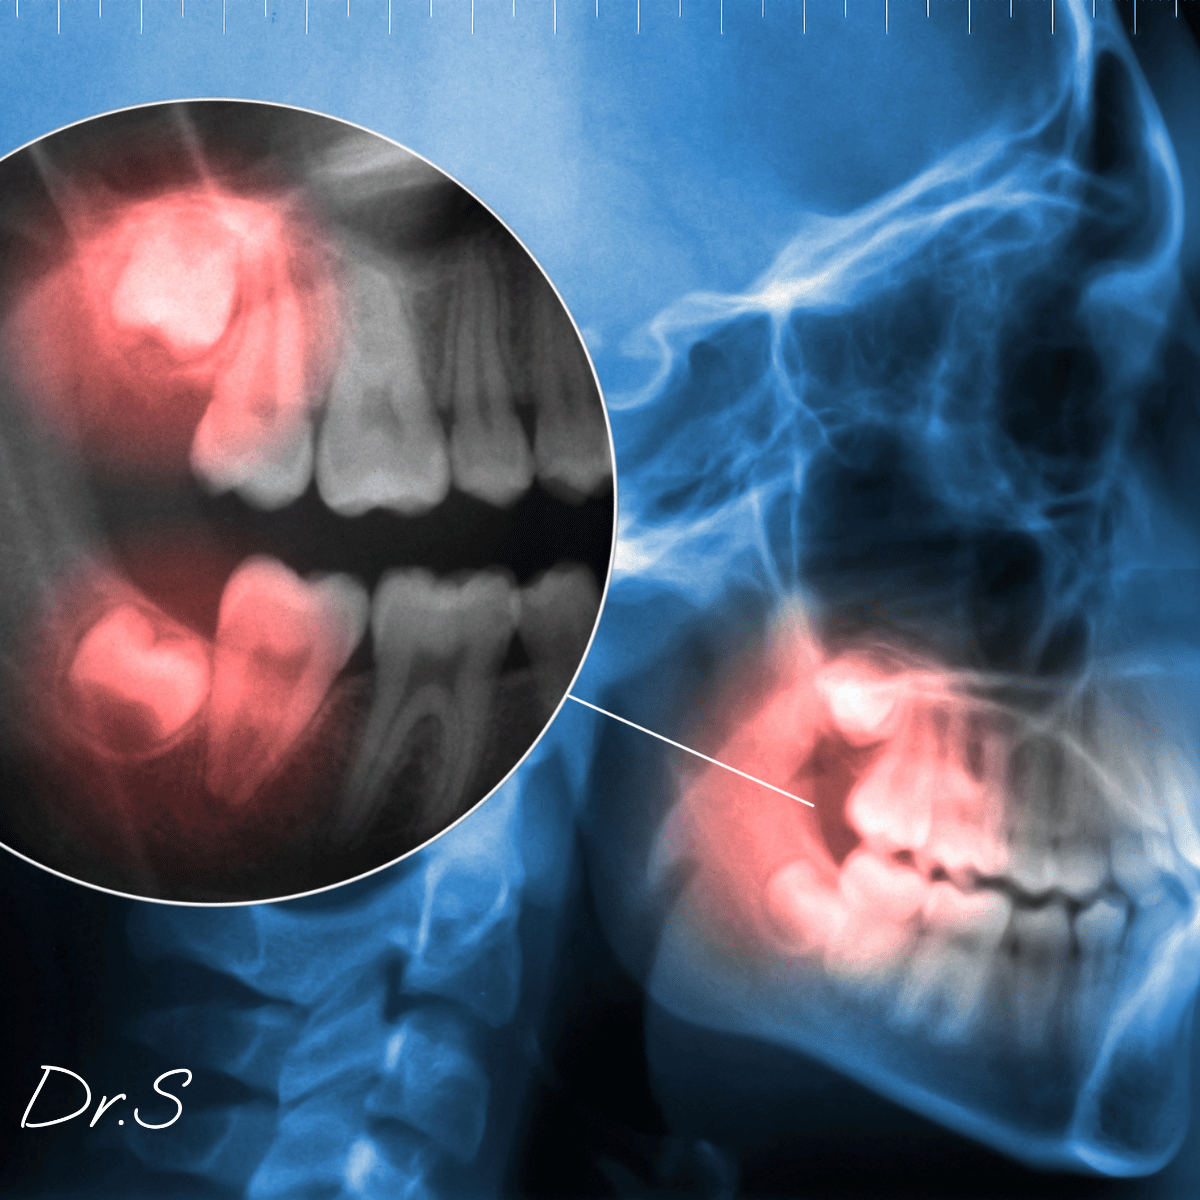

Une dent de sagesse qui pousse est l'une des dernières molaires à apparaître, souvent entre 16 et 25 ans. Elle peut entraîner douleur, gonflement ou gêne selon l’espace disponible et sa position.

Dans certains cas, la poussée peut déplacer les dents voisines, causer des chevauchements ou gêner l’alignement dentaire. Un contrôle est essentiel pour éviter des complications orthodontiques.

La dent de sagesse qui pousse apparaît généralement entre 17 et 25 ans, mais peut survenir plus tard. La durée est variable, allant de quelques jours de gêne à plusieurs mois, selon la vitesse de l’éruption et l’espace disponible.